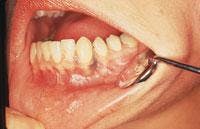

Intraoral examination revealed a solitary dark blue discoloration of the marginal gingiva facial to tooth #22 (see photo). The area appeared diffuse and measured approximately 5 mm by 4 mm in diameter. The bluish area would not blanch with pressure.Further oral examination revealed no other areas of the oral mucosa with a similar discoloration.